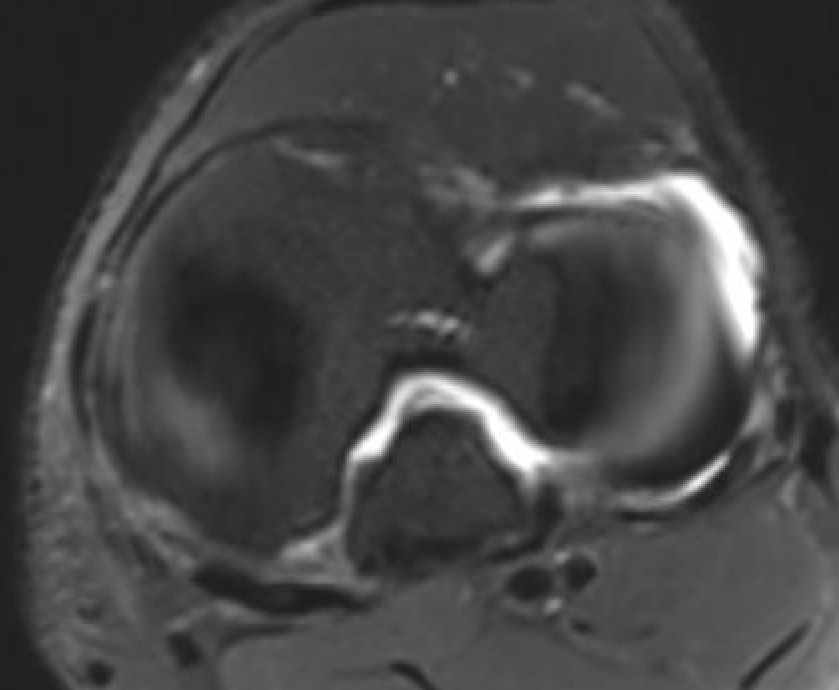

Posterior subluxation of tibia

Grade 3 PCL disruption - posterior tibia subluxed behind posterior aspect femoral condyles